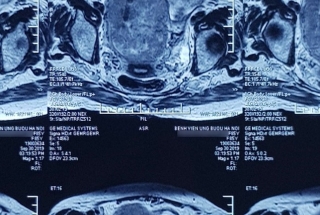

MỞ KHÍ QUẢN TƯ THẾ NẰM NGHIÊNG CHO BỆNH NHÂN U KHÍ QUẢN HIẾM GẶP

Các bác sĩ khoa Ngoại Đầu cổ - Bệnh viện Ung Bướu Hà Nội vừa phẫu thuật thành công, mở khí quản ở tư thế nằm nghiêng, cắt bỏ khối u khí phế quản trên cổ của một bệnh nhân 67 tuổi. Đây được xem là trường hợp rất hiếm gặp ở người cao tuổi. Hơn nữa, u khí phế quản thường nằm trong lồng ngực, nhưng bệnh nhân này u lại phát triển tại cổ gây khó thở dữ dội tăng dần, nguy cơ tử vong.